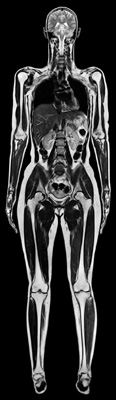

Total imaging matrix (Tim) is a new method of magnetic resonance

tomography introduced by Siemens Medical Solutions in 2004. It allows

whole-body imaging in a single examination with excellent image quality.

In addition, an examination with Tim allows for a multi territory

assessment through out of cardiovascular diseases throughout the entire body

in a single exam without patient repositioning, for example arteriosclerosis

and diabetes do not affect the heart alone, but other organs and vessel

systems as well. For diabetes, the kidneys in connection with the heart and

the entire vascular system can be examined in a single exam in high

resolution. The physician is able to diagnose vessel changes early and take

therapeutic measures before the heart muscle is damaged.